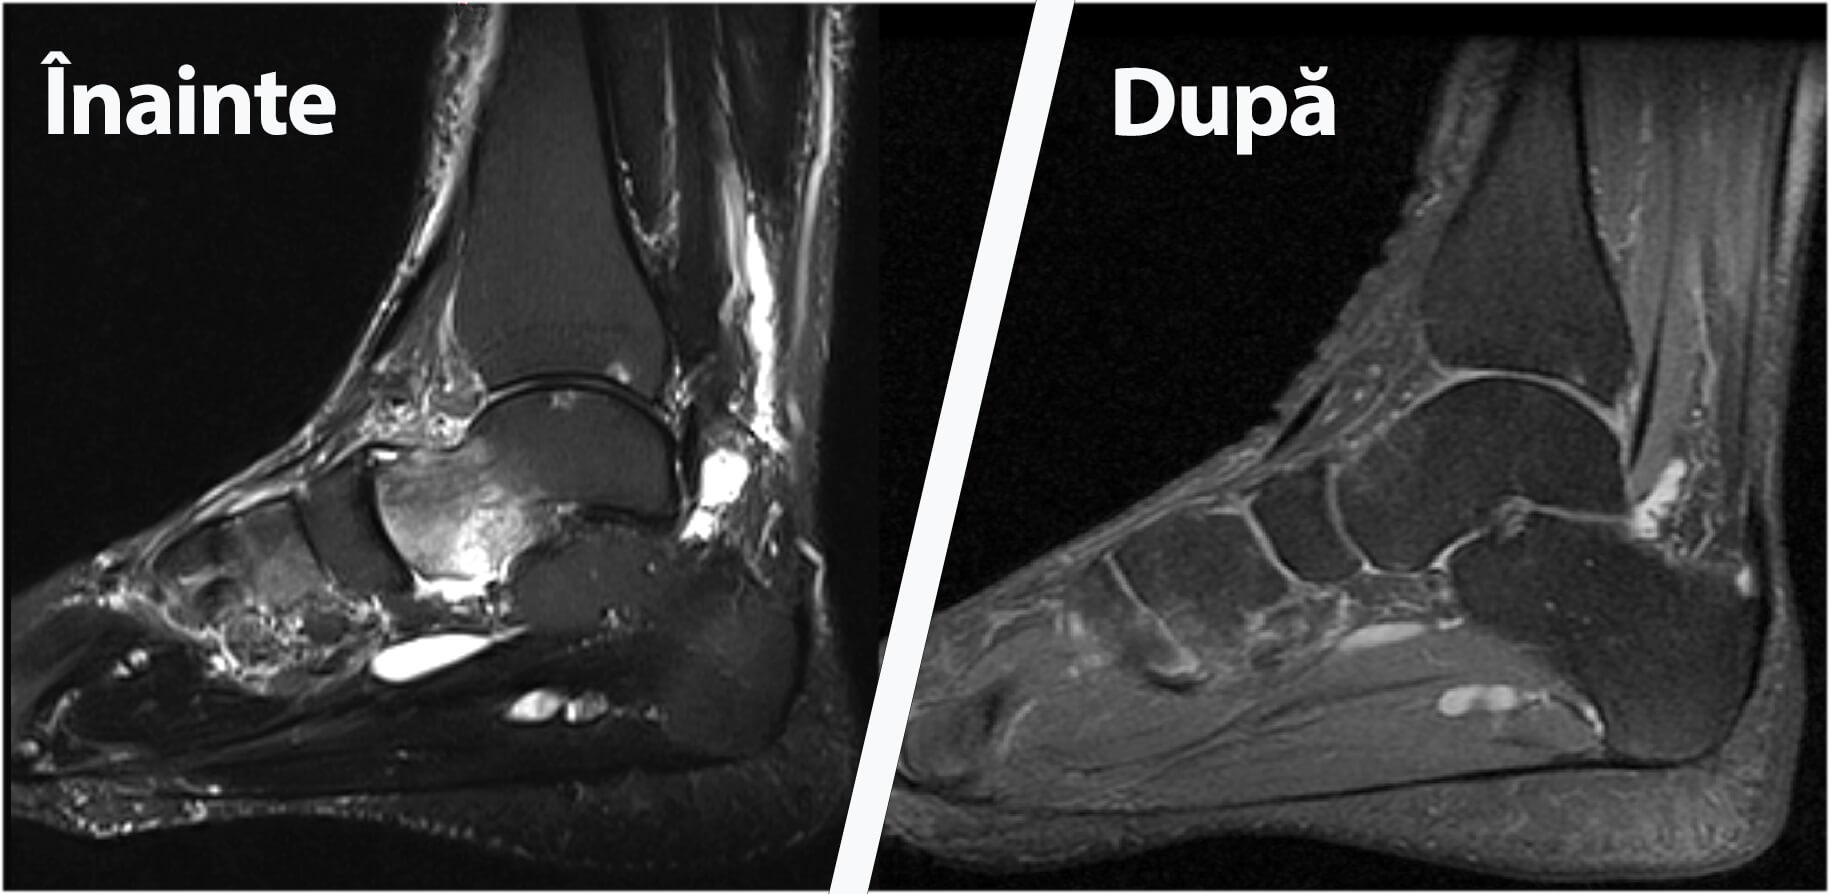

Casi studio: Prima e dopo

Scopri le trasformazioni dei nostri pazienti, ottenute presso la clinica Hyperbarium Oradea con la terapia iperbarica! I loro progressi, documentati prima e dopo il trattamento, evidenziano risultati impressionanti in diverse condizioni.